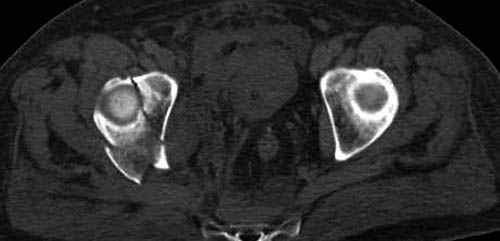

По возможности вышлите снимки, сканы таза до

реконструкции, интраоперационные.

По снимку создается впечатление о высоком поперечном переломе, задней колонны, стенки; почему не пользовались *magic screw*?

Снимки здесь....